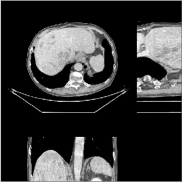

Fig.Β 10 shows the reconstructions (shown for the central axial, sagittal, and coronal planes in the 3D volume) for PWLS-EP and PWLS-ULTRA with patch-based weights () from low-dose abdomen scans. For the sagittal and coronal planes, we show the central out of axial slices. The supplement provides PWLS-EP reconstructions with different regularization strengths. The PWLS-ULTRA reconstructions in Fig.Β 10 have reduced noise as well as higher resolution, better structural details and shaper image edges than the PWLS-EP results. These results are further example of the potential performance of the proposed PWLS-ULTRA method in clinical settings.